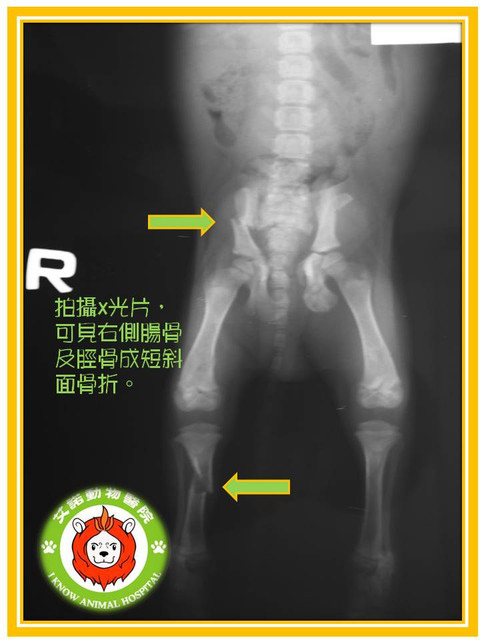

病例 年幼狗狗骨盆及小腿脛骨骨折 艾諾動物醫院的部落格 痞客邦